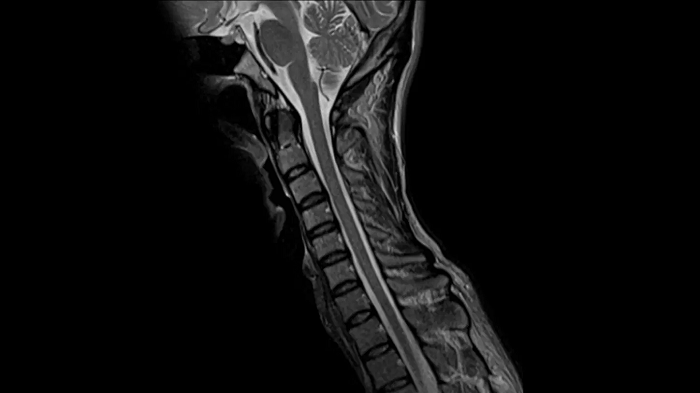

Spine

T2 TSE

Exceptional C-Spine images with T2 TSE with the use of the Head/Neck coil.

Deep Resolve Gain & Sharp

0.5 x 0.5 x 3.0 mm2

TA 3:28 minutes

MAC-ID: 7aaaa0164. Image Credit: Siemens Healthineers